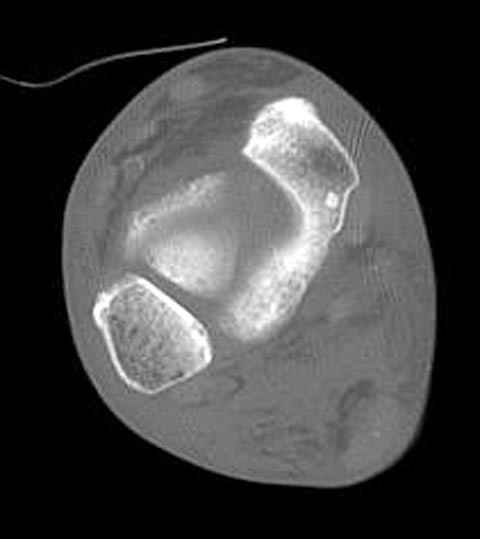

Уважаемые участники русского Ортофорума, поздравляю всех со всеми прошедшими праздниками: Новым годом, Рождеством, Hanukkah, Kwanzaa, желаю участникам всего наилучшего и здоровья.Повреждение таранной кости.Больной 81г автоавария, повреждение таранной кости, здесь снимки. Какие рекомендации?Djoldas Kuldjanov, MDDepartment of Orthopedic SurgerySt. Louis University Medical Center

В декабре у меня был пациент с политравмой и аналогичным повреждением тарана с подвывихом в таранно- ладьевидном суставе, единственное отличие - отломок головки тарана был меньше по размеру и фрагментирован, поэтому его фиксация была невозможна.

Для доступа к задне-медиальному суставному фрагменту я выполнил косую остеотомию внутренней лодыжки у её основания -получается хороший доступ к голеностопу, адекватный обзор и возможность восстановить суставную поверхность. фрагмент фиксировал двумя 3,5 мм спонгиозными винтами с неполной резьбой, *утопив* головки винтов в кость. Аналогичная фиксация и двумя тягловыми винтами и внутренней лодыжки. \в качестве альтернативы для

фиксации фрагмента тарана можно было бы использовать и герберт винты, но по организационным причинам :-(( набора не оказалось под рукой).

Вывих в таранно-ладьевидном суставе удалось вправить с помощью Howard retractor, используя его в качестве рычага.Сегодня искал в рентген архиве